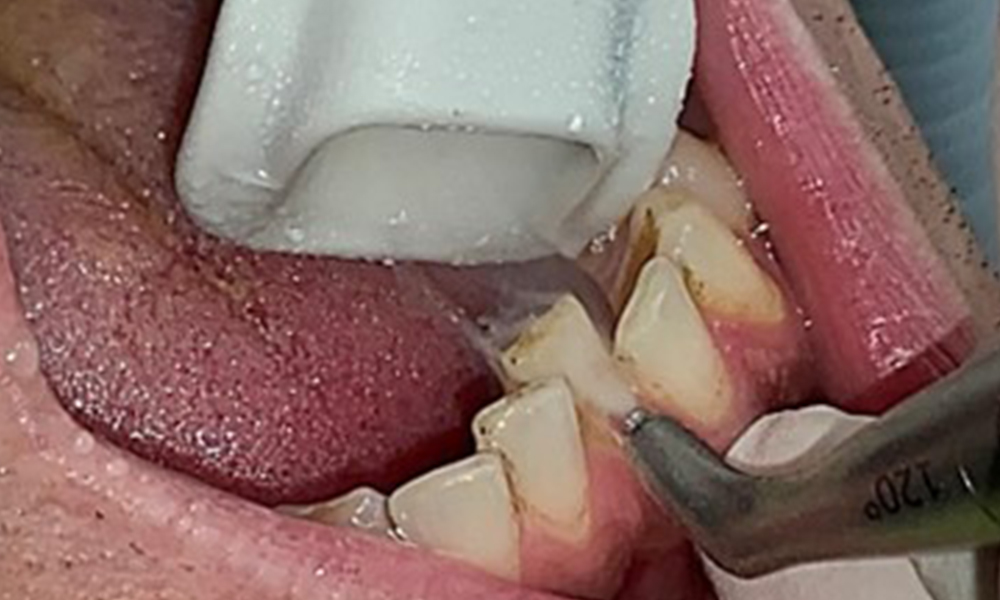

Taschensondierung (BOP) mit Darstellung der Rg. 36 lingual

Abb. 7 Taschensondierung (BOP) mit Darstellung der Rg. 36 lingual, © Dr. R. Krapf

Aufgrund des guten allgemeinmedizinischen Zustandes ist der aus der Mundgesundheit ermittelte Bedarf maßgebend für die Behandlung. Die regelmäßige Erhebung der Sondierungstiefen ist unabdingbar. Die gingivale Blutung ist bei Rauchern herabgesetzt, weswegen die klinische

Diagnose einer Parodontitis nur durch Sondierung möglich ist (Abb. 7). Die ausschließliche Erhebung von Blutungsindizes verdecken unter Umständen das Bild einer bestehenden Parodontitis oder Gingivitis. (5)